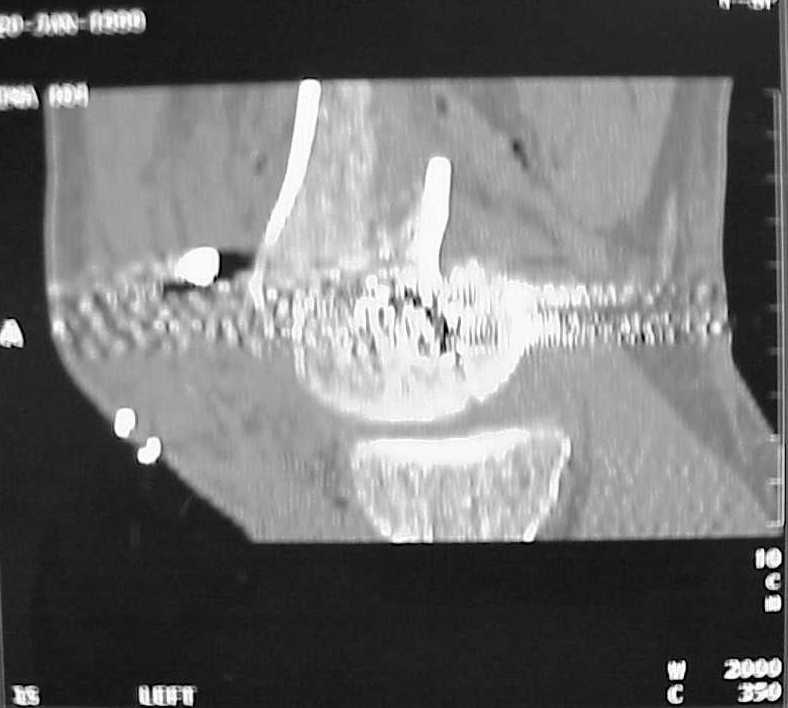

Мы пошли на операцию с планом попытаться сделать закрытый интрамедулярный, а не получится - сделать аппаратом. Посчитали, что получилось, хотя на еженедельной конференции ожидаются некоторые проблемы с объяснениями ;-)

Насчет стабильности для ранней нагрузки, конечно, сомнительно, но при таком повреждении ранняя нагрузка противопоказана в любом случае. Для ранних движений Должно хватить. Снимки в следующем сообщении.

воспользовались для репозиции, см. приложение.